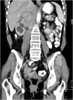

Extension of retroperitoneal mass

May Cause